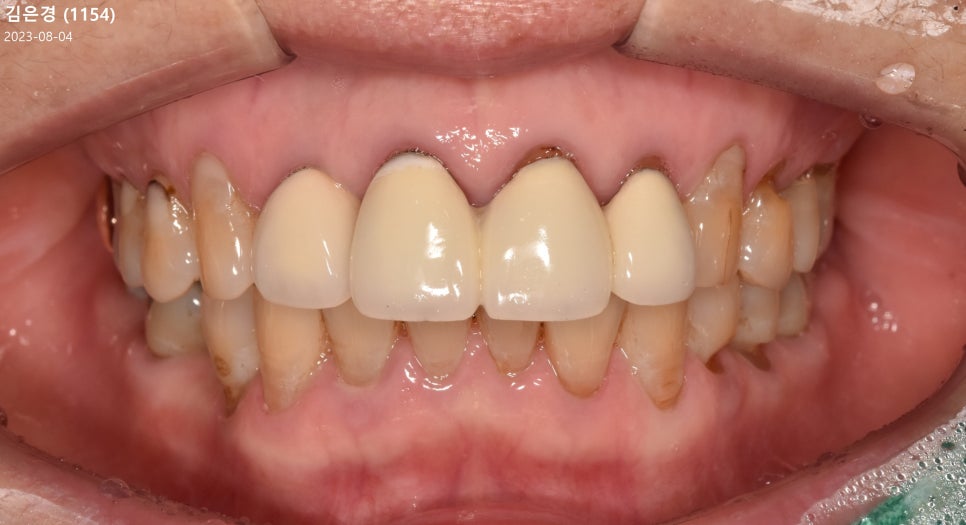

오늘 사례 속 환자는 치은 퇴축으로 인해

기존에 수복 받은 크라운 심미가 떨어진다며

이 문제를 개선하기 위해 내원하셨는데요.

환자의 구강 현황을 살펴 봤을 때

치아와 치은 경계부가 깎이고 패이는

치경부 마모증이 심하게 나타난 상황이고,

주소로 말씀하셨던 것처럼 치은이 내려가

전치부 크라운의 심미성이 떨어지고 있었습니다.